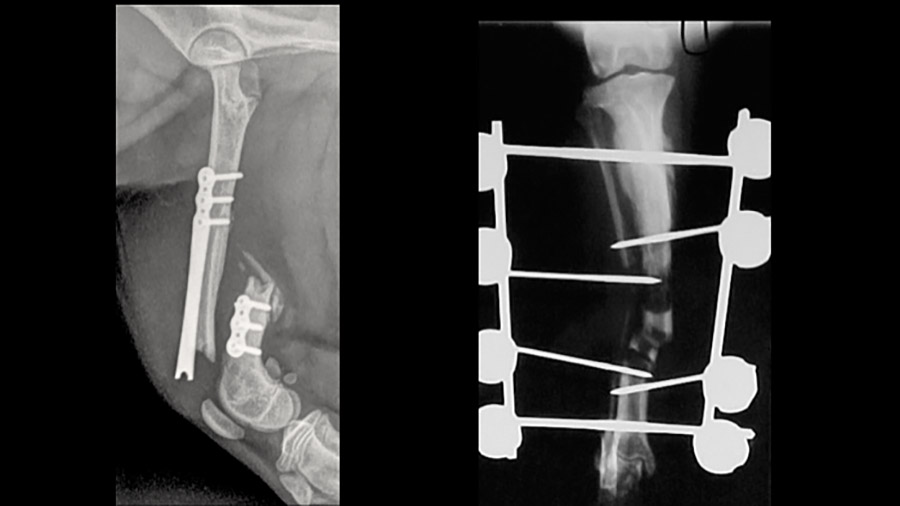

“You can have to ask which kind of osteosynthesis—rigid and stable or more elastic—is most appropriate. If you correctly answer the first question—whether the fracture is anatomically reducible—then you will sort out the corrective technique,” says Peirone. “One of the most common mistakes is mixing the principles—applying the wrong technique to a given fracture.”

Most postoperative complications involve implant failure, screw pullout, infections, delayed union or nonunion, Peirone adds, noting that the correct response depends on the complication itself.

“If the complication is infection, you do the surgery within one or two hours in a sterile operating room and a well-prepared surgeon and team,” he says. “For implant failure, the risk of complication is mainly related to the quality of the implant and how you apply it, and for the bone healing process, nonunion is typical if the surgical footprint is too severe on the soft tissue therefore limiting the vascular supply. The worst-case scenario is when you have to perform an amputation—but it’s very uncommon. Only after discussion with the owner do we go ahead with an amputation; it’s always bad, but our patients have four limbs, and a dog with three legs can have an acceptable quality of life.”